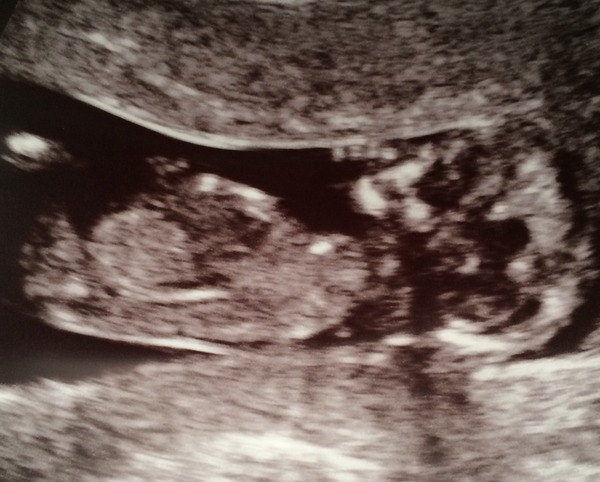

Yes just had my scan, was a bit stressful! Baby is fine from what we saw but she was lying in a difficult position, had to go away and have a walk and drink a litre of water - didn't move her at all! The guy doing the scan tried moving her (had me jump up and down too haha) but she was stubborn and stayed bum up facing away despite me contorting about.did see her kick when he pressed down and wriggle a bit!! Couldn't do the NT measurement so am going back in 2 weeks for second trimester bloods instead. Got a pic but it's v blurry!

And here's the best photo we got - have cleaned it up a bit so we can see a bit more, she looks fed up :D

The weird shadow is because she's all hunched up as high as she can get like she's trying to escape up through my stomach! Also because of my weird shaped uterus and how I was lying on my side. Basically everything about it was "weird" today haha

vicky yes I have a weird spot encroaching into my ear Shock I feel so unglamorous :( I think your baby looks like a girl, it's a cute photo, I wasn't as impressed with mine as I was with the private scan ones though. Did you get given a date for your 20 weeks scan?

I think boy for Southy and Storm and girl for Vicky! Lovely scan pics!

I'm guessing a boy for Southy and girls for Vicky and Storm [disclaimer: I have no idea about nubs!]